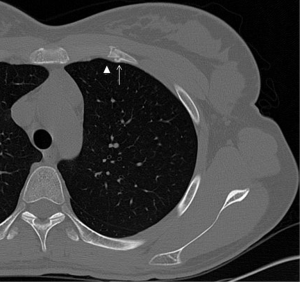

A nondisplaced rib fracture is defined as a rib fracture with complete cortical disruption but with maintained alignment, usually involving the medullar bone and both the inner and outer cortices (Figure 1); it is seen such a lucent line on radiographs or CT images (14). Stress rib fractures are overuse injuries that occur when there is an abnormal force on normal underlying bone. These begin with a small stress on the bone, which with repeat injury results in a microtrabecular fracture that may progress to rib fracture. These injuries are rare, although possibly underdiagnosed, and most often seen in workers who perform repetitive motions and athletes. Detection of non-displaced and stress rib fractures on radiographs is difficult, and these injuries may be seen radiographically only at follow-up imaging, after signs of healing have manifested (7). On the contrary, MRI can show immediately an area of oedema (high T2 signal) after a traumatic event. When cortical disruption and a substantial abnormality in alignment are evident, a rib fracture is classified as displaced. Displacement may be minimal or obvious. Displaced fractures may be identified on radiographs or CT images (Figure 1). Injury to the surrounding tissues and structures can occur, and several lethal complications such an aortic injury have been documented in the literature (15). A buckle fracture of the rib occurs when there is disruption of either the inner or outer cortex (Figure 2) with no observable fracture of the other cortex (16). Some researchers have reported that the term buckle is derived from engineering terminology that describes disruption of the inner or tensile side of a structure that is placed under force (7,17). Flail chest (“volet”) is a traumatic condition in which there are three or more contiguous ribs with fractures in two or more places (Figure 3). Fractures usually occur in the anterior and anterolateral portions of the middle to lower ribs (1). These fractures create a flail segment that can move paradoxically relative to the remainder of the chest during respiration in a spontaneously ventilating patient. Although imaging can show fractures, it is the clinical examination that will demonstrate paradoxical motion. Flail chest serves as a marker for significant intrathoracic injury, since more than one-half of the affected patients may have associated injuries that require surgical treatment (18).

Sternal fractures may result from deceleration injuries or direct blows to the anterior chest wall. Fractures commonly involve the sternal body and the manubrium. Although sternal fractures have been viewed as a marker for high-energy trauma (21), a simple sternal fracture may also occur as an isolated injury (22). However, displaced sternal fractures and those with associated manubrial-sternal joint disruption frequently occur with an association to thoracic, cardiac, and spinal injuries. Sternal fractures are best demonstrated on multiplanar reformatted CT images (Figures 7,8). Occasionally, a fracture line may be difficult to detect on axial CT, and the presence of anterior mediastinal haemorrhage could be the clue for diagnosis (1). Some anatomical variants can be expected (Figure 9); for instance, the xiphoid process has several morphologic variants (pointed, oval, and forked shapes; one, two or more xiphoid foramina) that are well evaluated by MDCT (23,24). These findings should be kept in mind for avoiding diagnostic imaging mistakes.